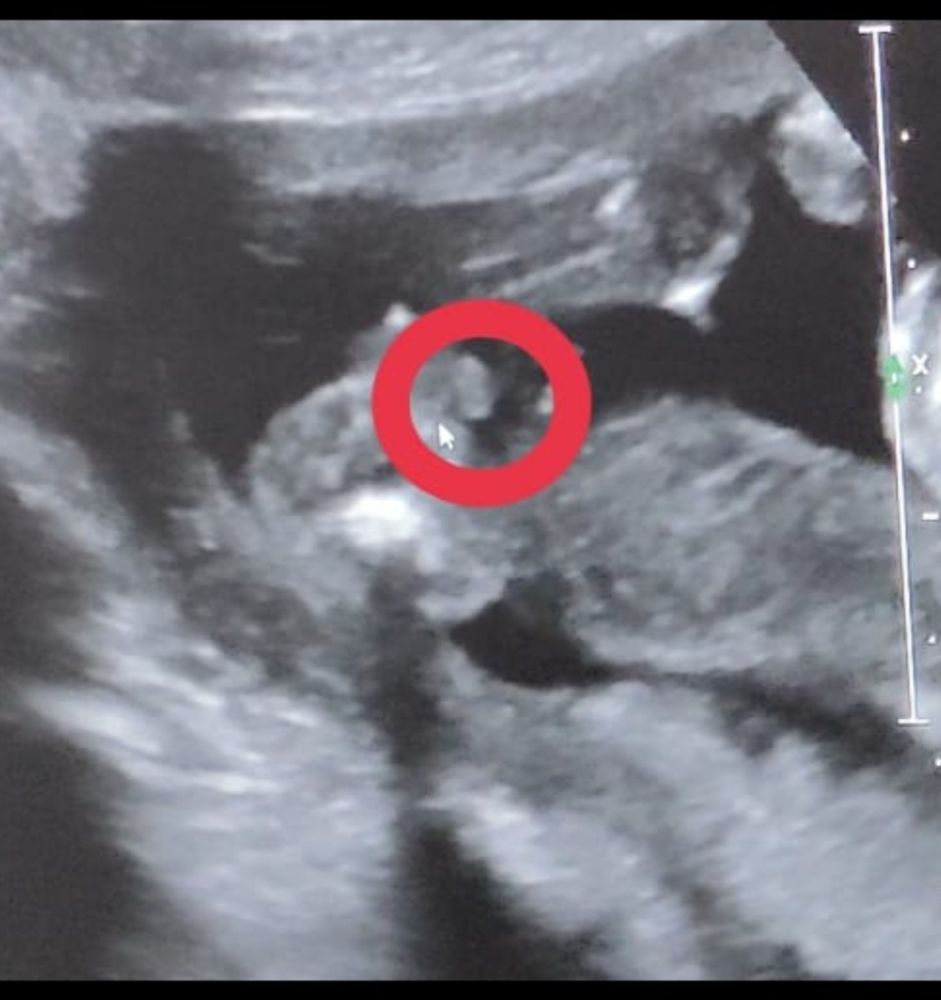

Пришли к УЗИсту узнать пол до скрининга, который сказал, что у меня замершая на 90 проц🤣УЗИст может узнал меня, сказал бесплатно скажет. А мы теперь ему до конца не доверяем. Мышкой показывает мошонку, а мы не совсем понимаем, так как смотрели минуту🤣 как будто справа ноги согнутые и булки понятно

Я, когда видео идёт, видно, что смотрим снизу на булки, ноги согнутые, а что за большой круг не понимаем

Кристина, когда видео идёт, видно, что смотрим снизу на булки, ноги согнутые, а что за большой круг не понимаем

Похоже на мальчика, да. За точность не отвечаю 🤭 Там же внизу попа, указатель мышки на мошонке?

А там мошонка и ещё что-то 🤭